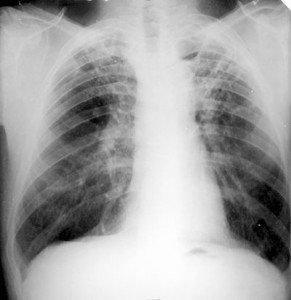

La tasa española de casos de tuberculosis está por encima de la media europea

España tiene una tasa de incidencia de tuberculosis superior a la media europa, con 17 casos por 100.000 habitantes. Así se ha puesto de manifiesto en el XV congreso de la Sociedad Española de Enfermedades Infecciosas y Microbiología Clínica que se celebra en Málaga, con la participación de unos 1.300 expertos.

El presidente del comité organizador del congreso y jefe del servicio de enfermedades infecciosas del Hospital Regional Carlos Haya, Juan de Dios Colmenero, en declaraciones realizadas a este periódico, indicó que en España nunca ha llegado a estar erradicada la tuberculosis, puesto que siempre ha habido un foco de esta enfermedad infecciosa. «La tuberculosis ahora se mantiene en una situación muy estable. La mayoría de los casos se dan en personas inmunodeprimidas o que viven en una situación social de precariedad», señaló Colmenero.

El mayor problema al que se enfrentan los médicos en este padecimiento es que los enfermos que están en un mal entorno social no cumplen los tratamientos. Al no cumplirlos, la cadena de contagios se perpetúa. Por eso es fundamental hacer diagnósticos precoces y conseguir un cumplimiento correcto del tratamiento. Cuando se lleva cabo, está demostrado que la tasa de incidencia de la tuberculosis disminuye de forma sostenida, apostilló el doctor Colmenero.